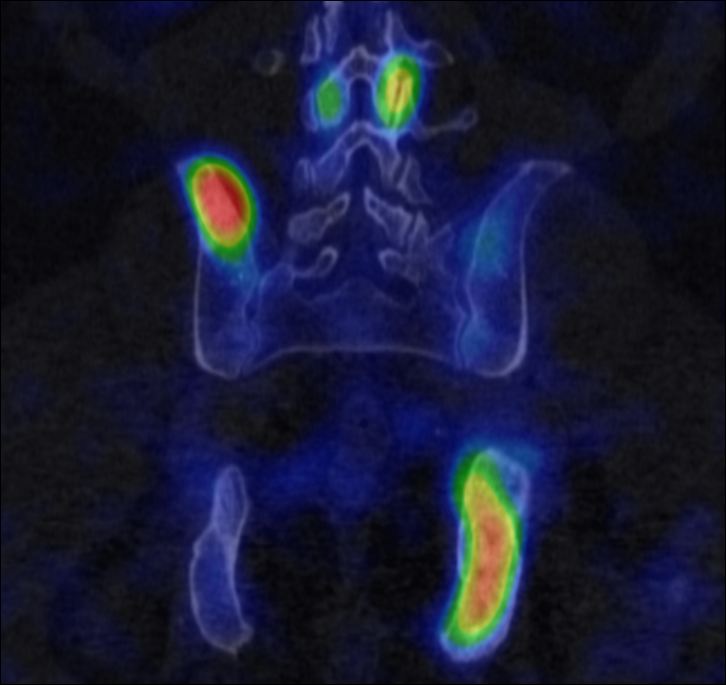

The most common clinical use of FDG-PET is in the form of whole-body scan, with oncologic indications. The majority of malignant tumors operate with higher energy consumption and show an increased glucose metabolism, consequently an increased uptake of FDG. The grade of malignancy is usually proportional to the rate of uptake. This method is useful in oncologic diagnostics, since it is capable to differentiate benign lesions from malignant ones. Whole-body PET imaging is capable to detect the primary tumor with local nodal metastases as well as distant metastatic lesions (staging) in one examination. (Figure 10.)

Test iframe

a

Image

b

c

d

10. Ewing’s sarcoma in the right humerus. Staging FDG PET-CT. PET Maximum Intensity Projection (MIP) image (a), transversal (b,c) and coronal (d) plane fused PET-CT images. Multiplex metastatic process with nodal, lung and bone involvement.